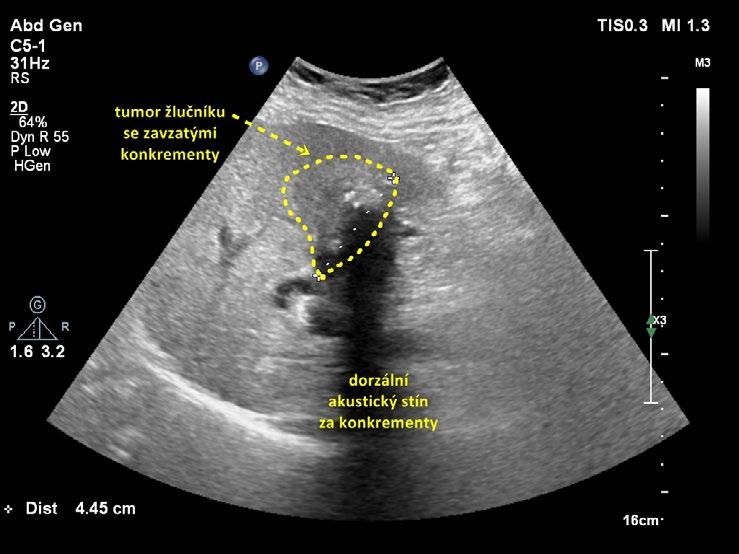

• lokálně pokročilý tumor žlučníku , který spotřeboval celé lumen žlučníku (obr. 1.19);

Obr. 1.19 Lokálně pokročilý tumor žlučníku